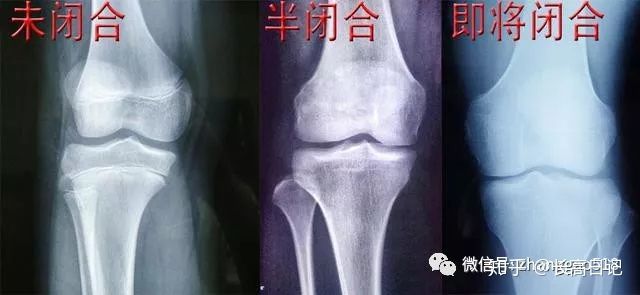

传统医学认为 骨骼线闭合后 身高就停止生长 ,身高增高最快速的时期,男性是11-18岁,女性为9-16岁。直到成年时,大多数人骨骺线开始处于休眠状态,到了20岁以后,开始逐渐趋于闭合。

但是有一点需要注意的是,人体的骨骺线闭合是一个极为漫长的过程,一般18-25处于半闭合状态,25-32岁之间处于即将闭合或者闭合状态。闭合前都有促进骨骼生长的可能。